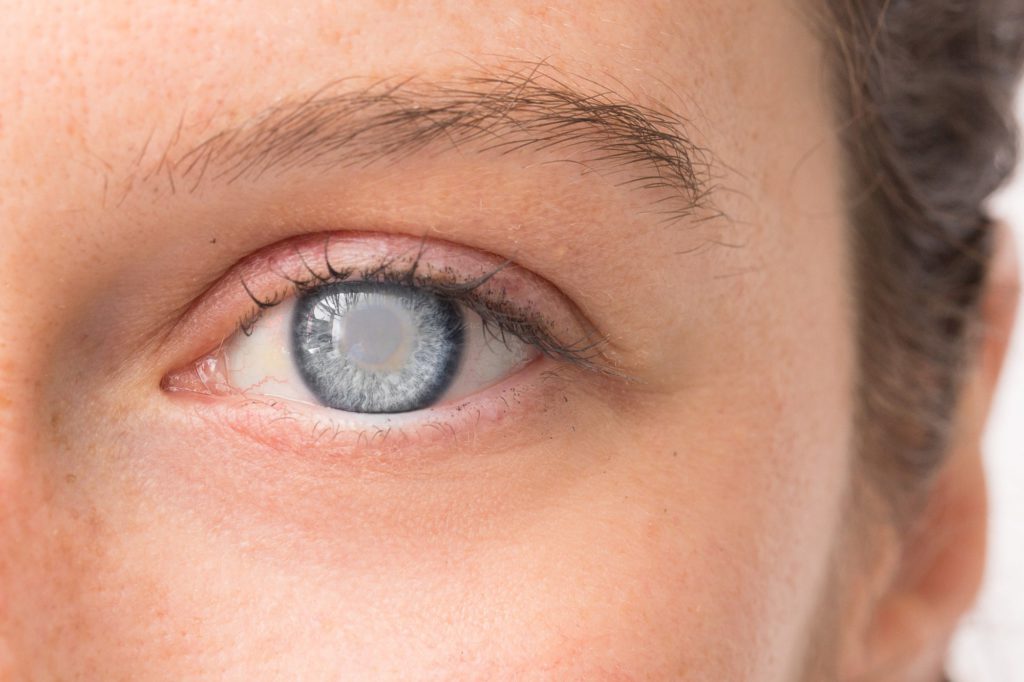

• Eyes Disorders

Eyes Disorders: Spectacles, Squint eyes, etc. 'Netra Tarpan'treatment.